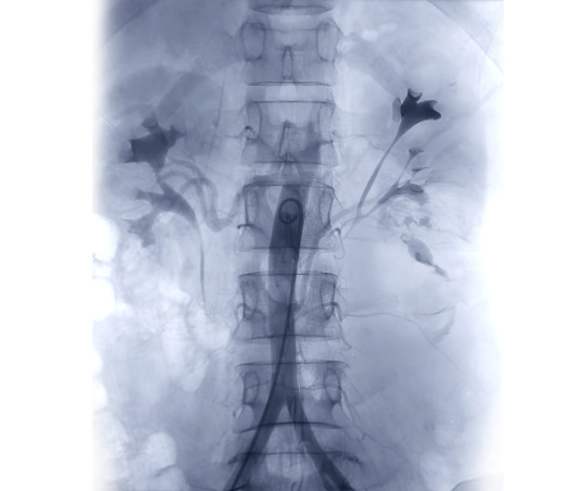

Хирург транскутанно выполняет пункцию радиальной, плечевой или бедренной артерии или вены, селективно вводит контрастное вещество в целевое артериальное или венозное русло для фиксации сосудистой патологии, далее, с помощью направляющего катетера, вводит внутри-сосудистые проводники диаметром (0,035'', 0,018'', 0,014'') до целевого сосудистого бассейна и по системе «monorail» доставляет катетер для эмболизации. Выполняет неселективную или селективную эмболизацию сосудистого русла эмболизационными спиралями или микрочастицами. Конечный результат фиксирует контрастным заполнением сосудистого бассейна на ангиографе в различных проекциях. После выполнения исследования хирургический инструментарий удаляется и выполняется гемостаз сосудистого доступа.